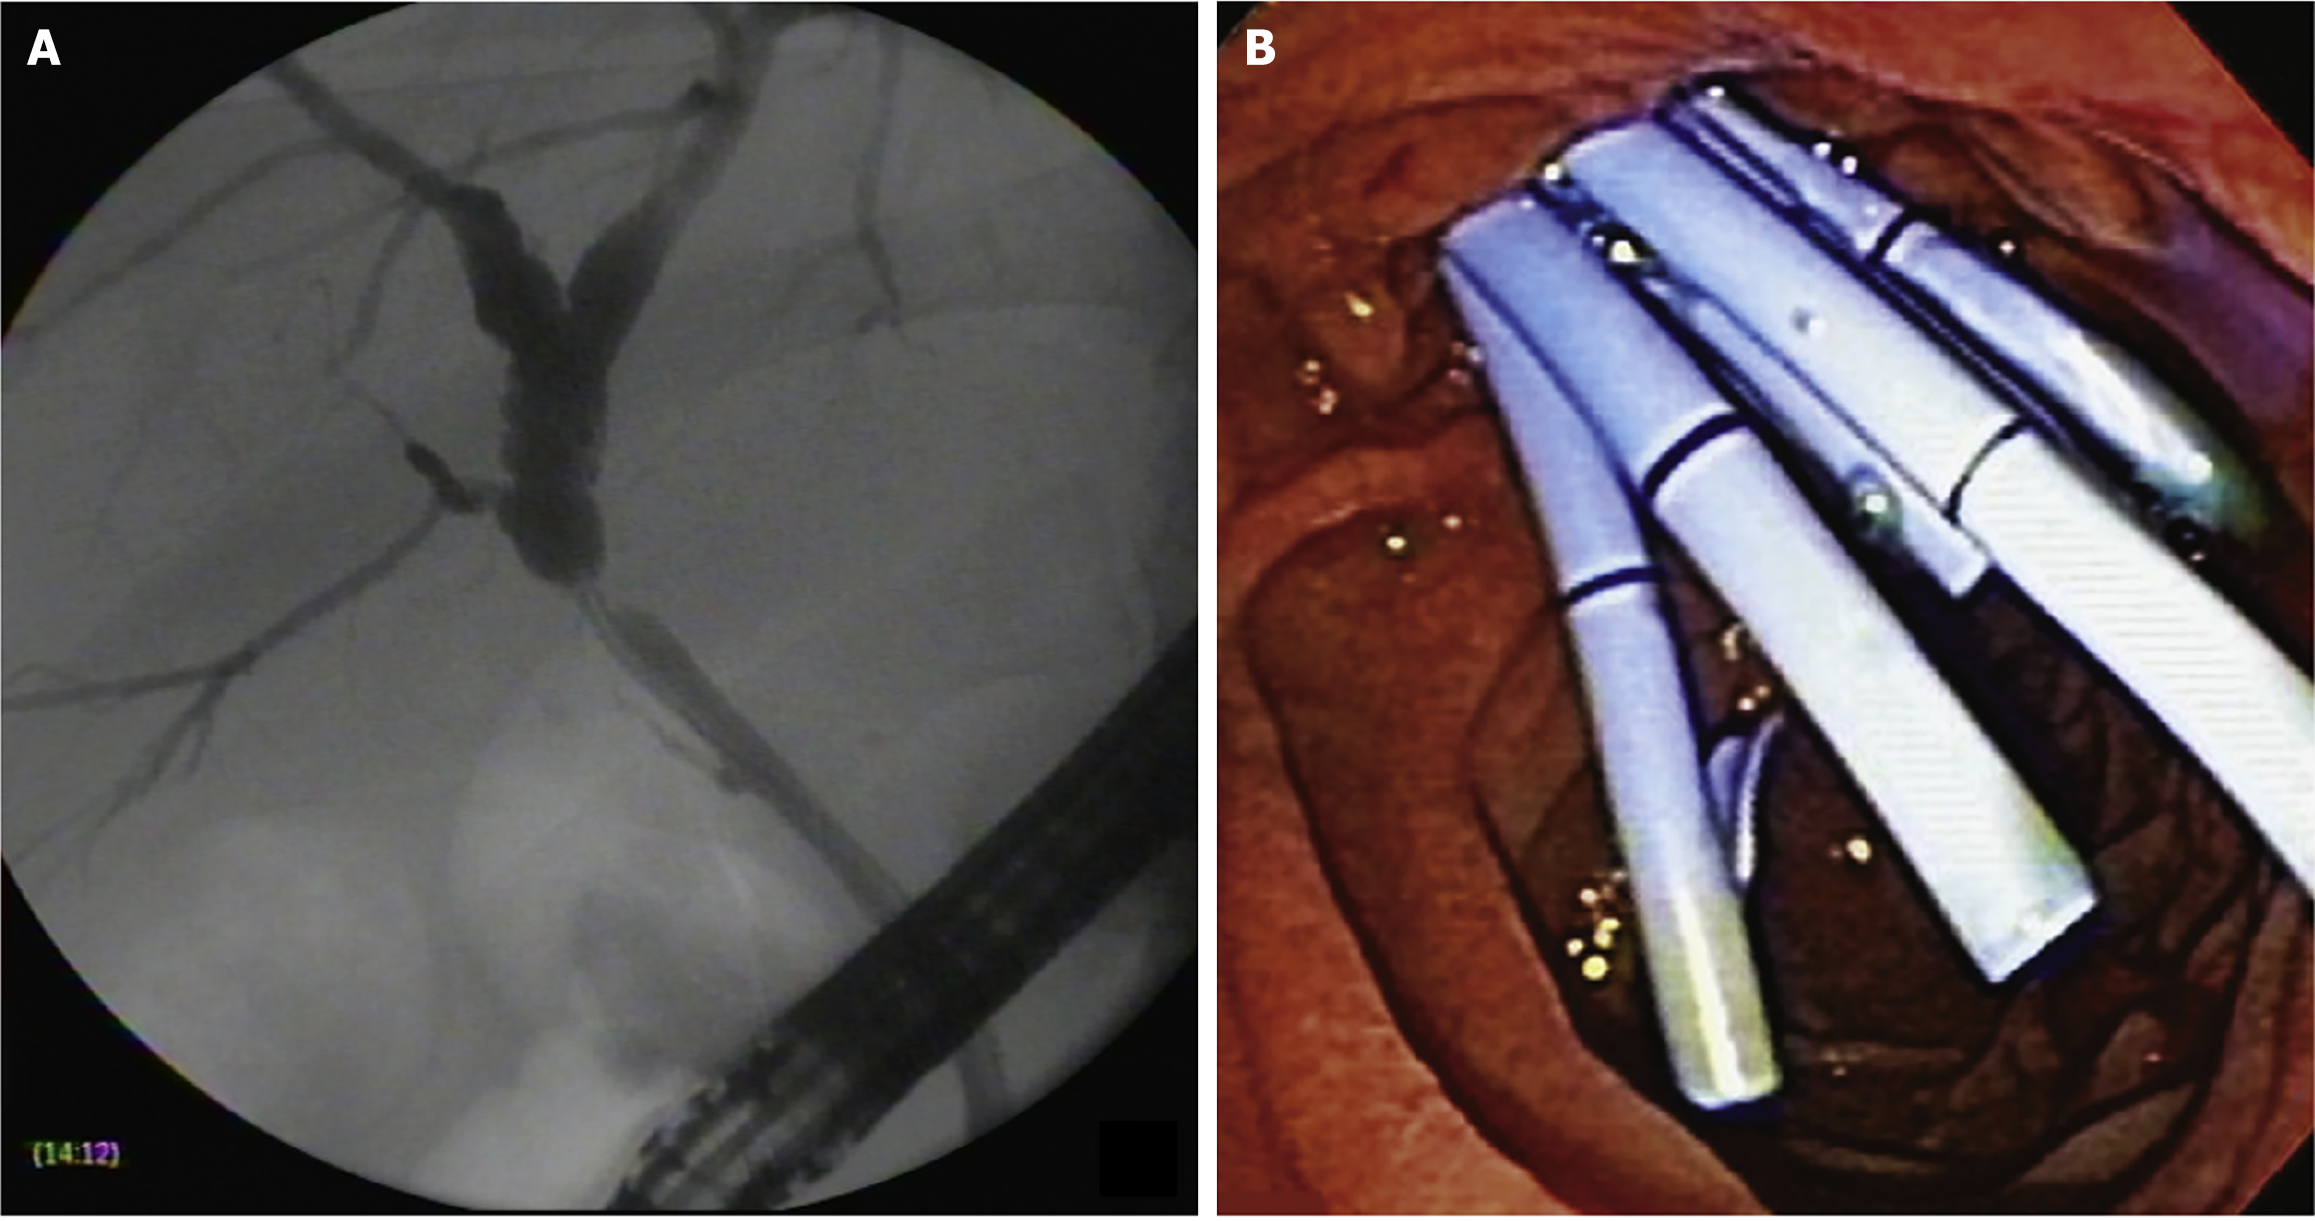

At the beginning of the study period, patients treated with cSEMSs had their stent removed after 6 months. Later in the study, with new evidence from the literature, the cSEMS were removed after 12 months. Patients were monitored for clinical signs of cholestasis. ERCP was performed whenever necessary at any time during follow-up. Patients without complications were followed for at least 12 months to remove the stent and evaluate stricture resolution. Patients who developed BASs within 30 days of liver transplantation were initially treated with MPS placement. If the stricture persisted following stent removal, the patients were re-evaluated for further treatment with MPSs. The treatment strategies using MPSs and cSEMSs are shown in Figures 1 and 2, respectively.

Stricture resolution: Overall stricture resolution occurred in 101/104 patients (97.1%): (1) 83/84 (99%) in the cSEMS group; and (2) 18/20 (90%) in the MPS group (P = 0.094). There was no difference between the cSEMS and MPS groups after an average 3-year follow-up. Endoscopic failure occurred in 3 patients: (1) Two in the MPS group; and (2) One in the cSEMS group. All were referred for surgery (Roux-en-Y bilioenteric anastomosis) (Figure 4).